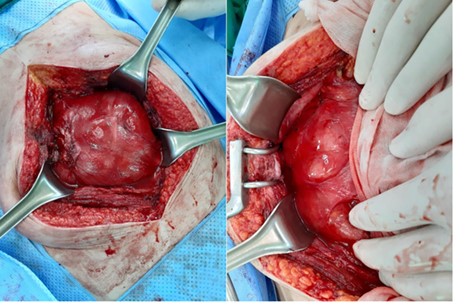

Conservative treatment had no effect on the patient and exploratory laparotomy was performed. On exploration, there were a dense fibrous sac encasing the entire small intestine and dense adhesions between intestinal loops. We performed excision of the membrane off the intestinal surface, complete enterolysis with release of the bowel loops, and resection and anastomosis of small bowel that caused obstruction (Figs. 2 and 3).

Whole small intestine is encapsulated in a dense fibrous membrane.

After excision of the membrane off the intestinal surface and complete enterolysis.